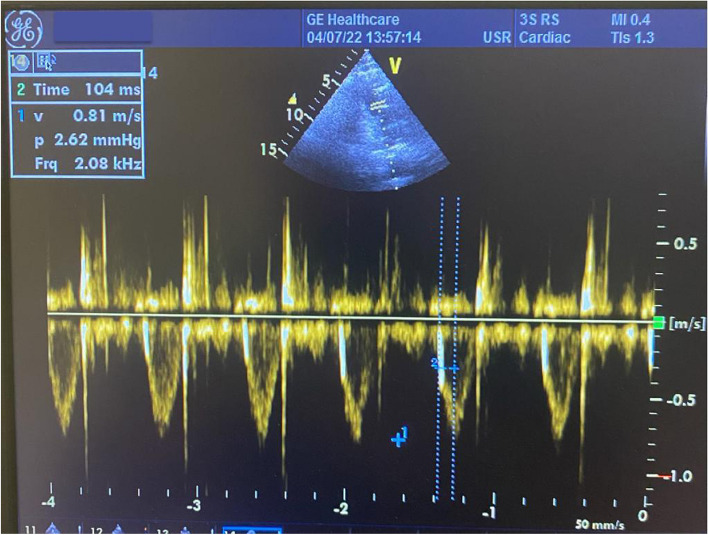

Methods: In total, 201 patients with prior COVID-19 infection without hospitalization and 195 healthy, age- and sex-matched individuals without a history of COVID-19 disease were included in this prospective analysis. The PAS value for each patient was calculated by dividing the mean peak pulmonary flow velocity by the pulmonary flow acceleration time.